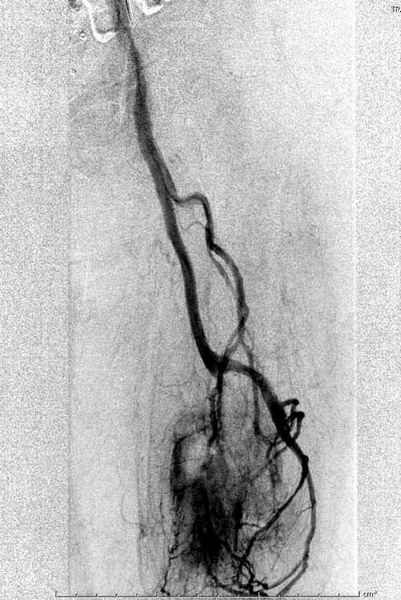

В зависимости от характера опухоли некоторые патологические переломы имеют риск кровотечения во время операции. Множественные литературные данные подтверждают, что надо проявить осторожность при интрамедуллярном остеосинтезе при неизвестных опухолях, особенно где имеется подозрение на Renal Cell Carcinoma. (RCC- hypernephroma) http://www.bonetumor.org/tumors/pages/page64.html

Со слов, больная ничем не болела, только последние 3 месяцев чувствовала боли в бедренной области. КТ брюшной полости подтвердил увеличенную правую почку. (5-6)

Для предупреждения кровотечения во время рассверливания, за день до операции провели эмболизацию сосудов питающий метастаз. http://radiology.rsnajnls.org/cgi/reprint/150/3/673.pdf (7-11, 12-15-16)